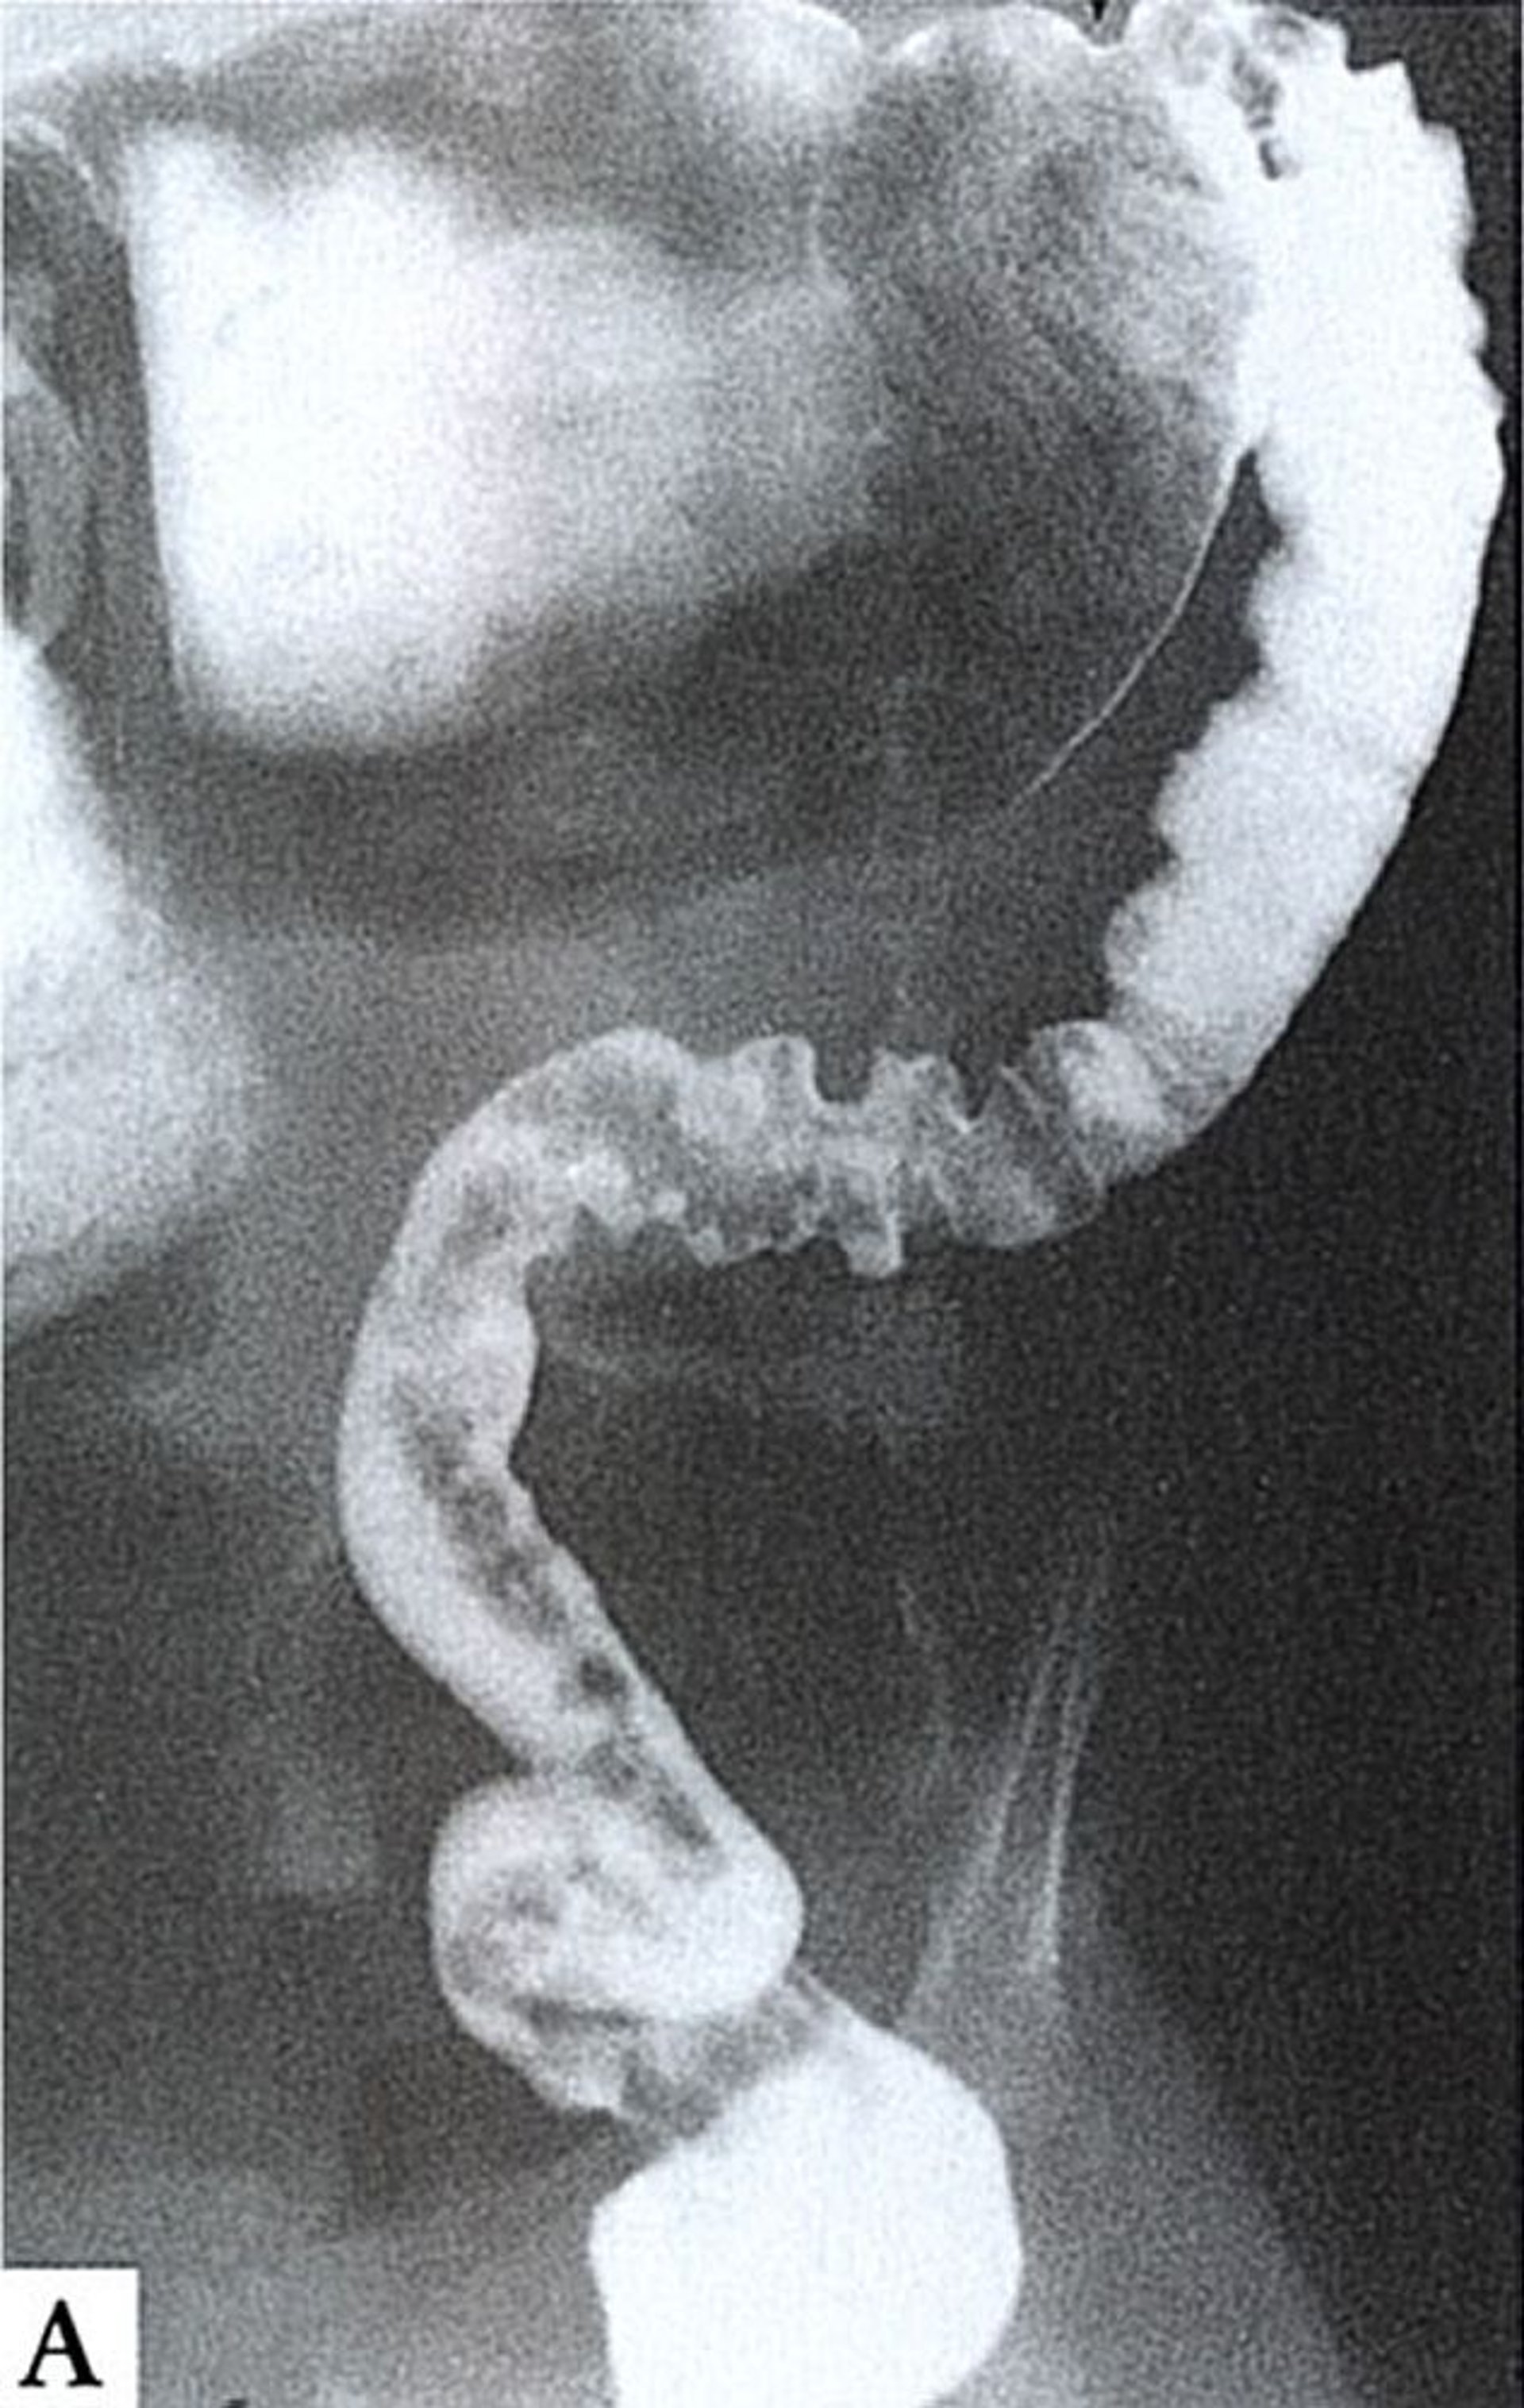

Enfermedad de Hirschsprung

Este enema de bario muestra aganglionosis por encima del ángulo esplénico. El intestino agangliónico es más estrecho y espástico (derecha), mientras que el intestino proximal, con inervación normal (arriba), está dilatado y lleno de materia fecal.